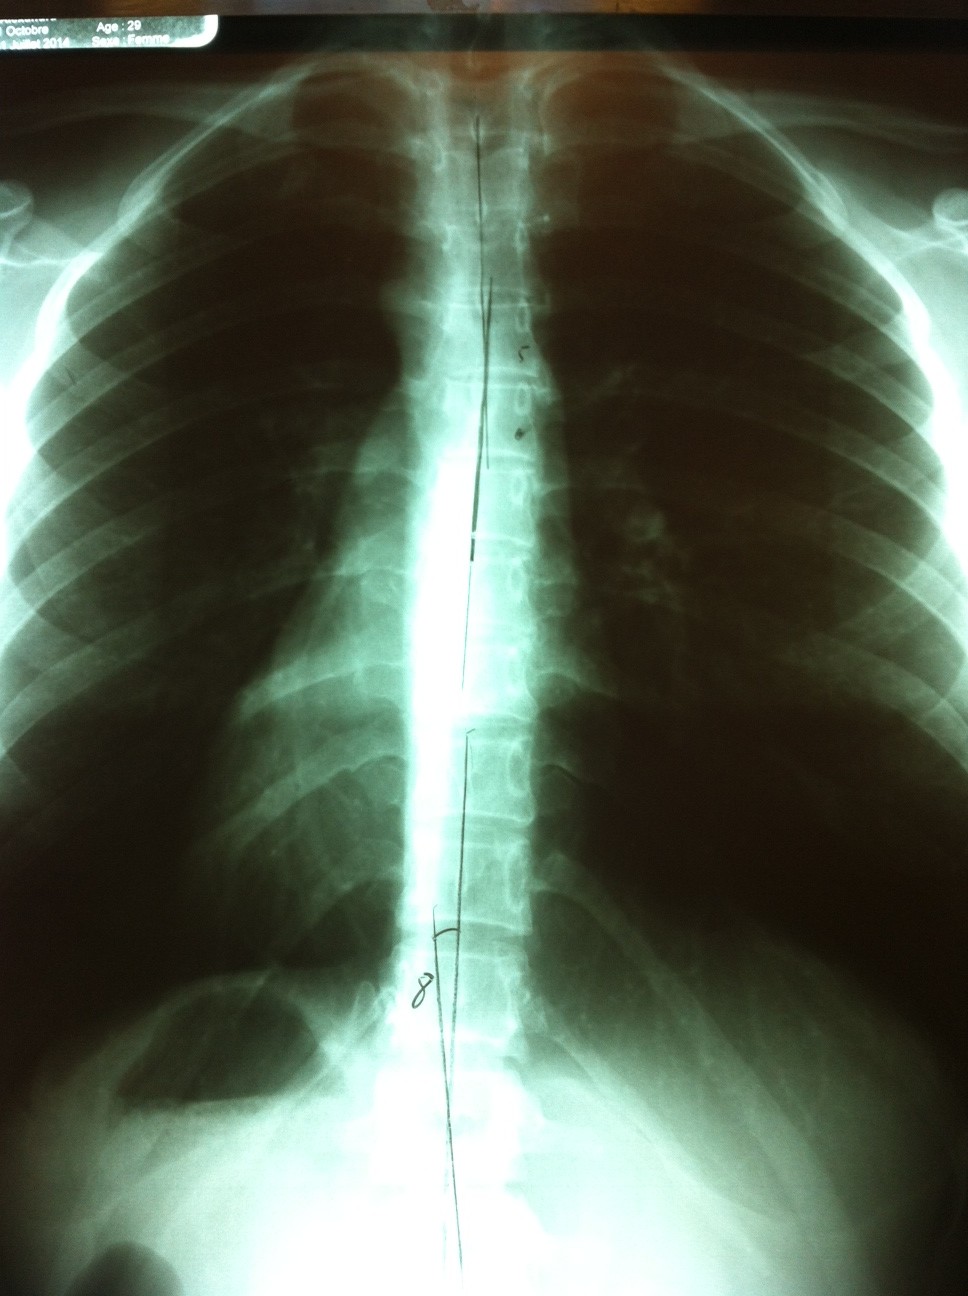

Lors de ma première visite chez le chiro, il a refait pratiquement le même traitement que l’ostéo (craquement des vertèbres T4-T5) et le mal était revenu en force. Suite à ce résultat, il a pris des radiographies et a découvert que la source du problème se trouvait plutôt dans une déviation de 5 degrés dans le haut de ma colonne, ce qui coince un nerf . Mon traitement consiste donc maintenant à environ 2 minutes d’ultrasons et quelques craquements (sérieusement pas une fan de ça mais, si ça aide, je suis prête à le faire). Selon mon chiro, je ne pourrai probablement pas refaire de musculation avant 3 à 4 semaines mais je suis capable de vivre avec ça. J’ai quand même le droit de faire des exercices pour le bas du corps tant que je ne prends pas de poids dans mes mains ou sur mes épaules. Ok doc! N’importe quoi pour que ça parte!

Bon, j’espère qu’une image de radio ne vous coupe pas l’appétit parce que j’ai une simili recette pour vous aujourd’hui! Une 100% de mon cru en plus, rien de moins…